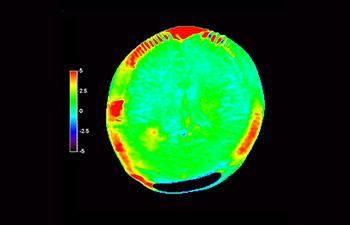

Glioblastom image

Gehirn mit Glioblastom

mit 3D APT